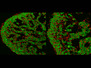

Spawning Nerves

The neurons [brain cells] in this image – in its entirety as wide as a human hair – were grown from stem cells which, when given the right signals, can become any sort of body cell. Neurons have a nucleus (here coloured blue) and a long tail – an axon (red), commonly known as a nerve. A protein known as 4R tau is highlighted in the axons with a green stain. Normally, neurons grown from stem cells have only a small amount of 4R tau protein, but scientists genetically modified these cells to produce much more. An imbalance in the amount of 4R tau relative to other proteins has been found in the brains of people with Parkinson’s and Alzheimer’s diseases. Looking at genetically modified neurons in the lab could yield clues about the relevance of 4R tau imbalance for degenerative brain disease.